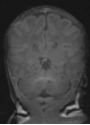

For the preterm infant, the provision of diagnostic measurements of brain compromise is a high priority, in order to minimise the risk of developmental impairment. Amplitude-integrated electroencephalography (aEEG) is used to monitor the functional status of the brain and to observe maturational changes during extrauterine development. Near-infrared spectroscopy (NIRS) enables continuous estimation of cerebral oxygenation. General movements (GM) are part of the spontaneous movement repertoire of newborn infants. The presence, quality and intensity of GM are markers of central nervous system integrity. Quality of GM has emerged as a reliable predictor of neurodevelopmental delay in preterm infants. Cerebral magnetic resonance imaging (MRI), performed at term-equivalent age in all very preterm infants, provides detailed information on the wide spectrum of preterm brain injury and alterations in postnatal brain development in preterm infants (Fig. 1).